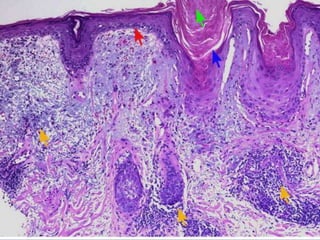

• Hyperkeratosis with keratin plugging down into spinous

layer alternating with areas of Atrophic retepegs

• Liquefaction degeneration of basal cell layer with thickening

of basement membrane

• Perivascular infiltration of lymphocytes along with

infiltration around dermal appendages,

• Basophilic degeneration of collagen and elastic fibers with

hyalinization,

• Edema and fibrinoid change juxta-epithelially